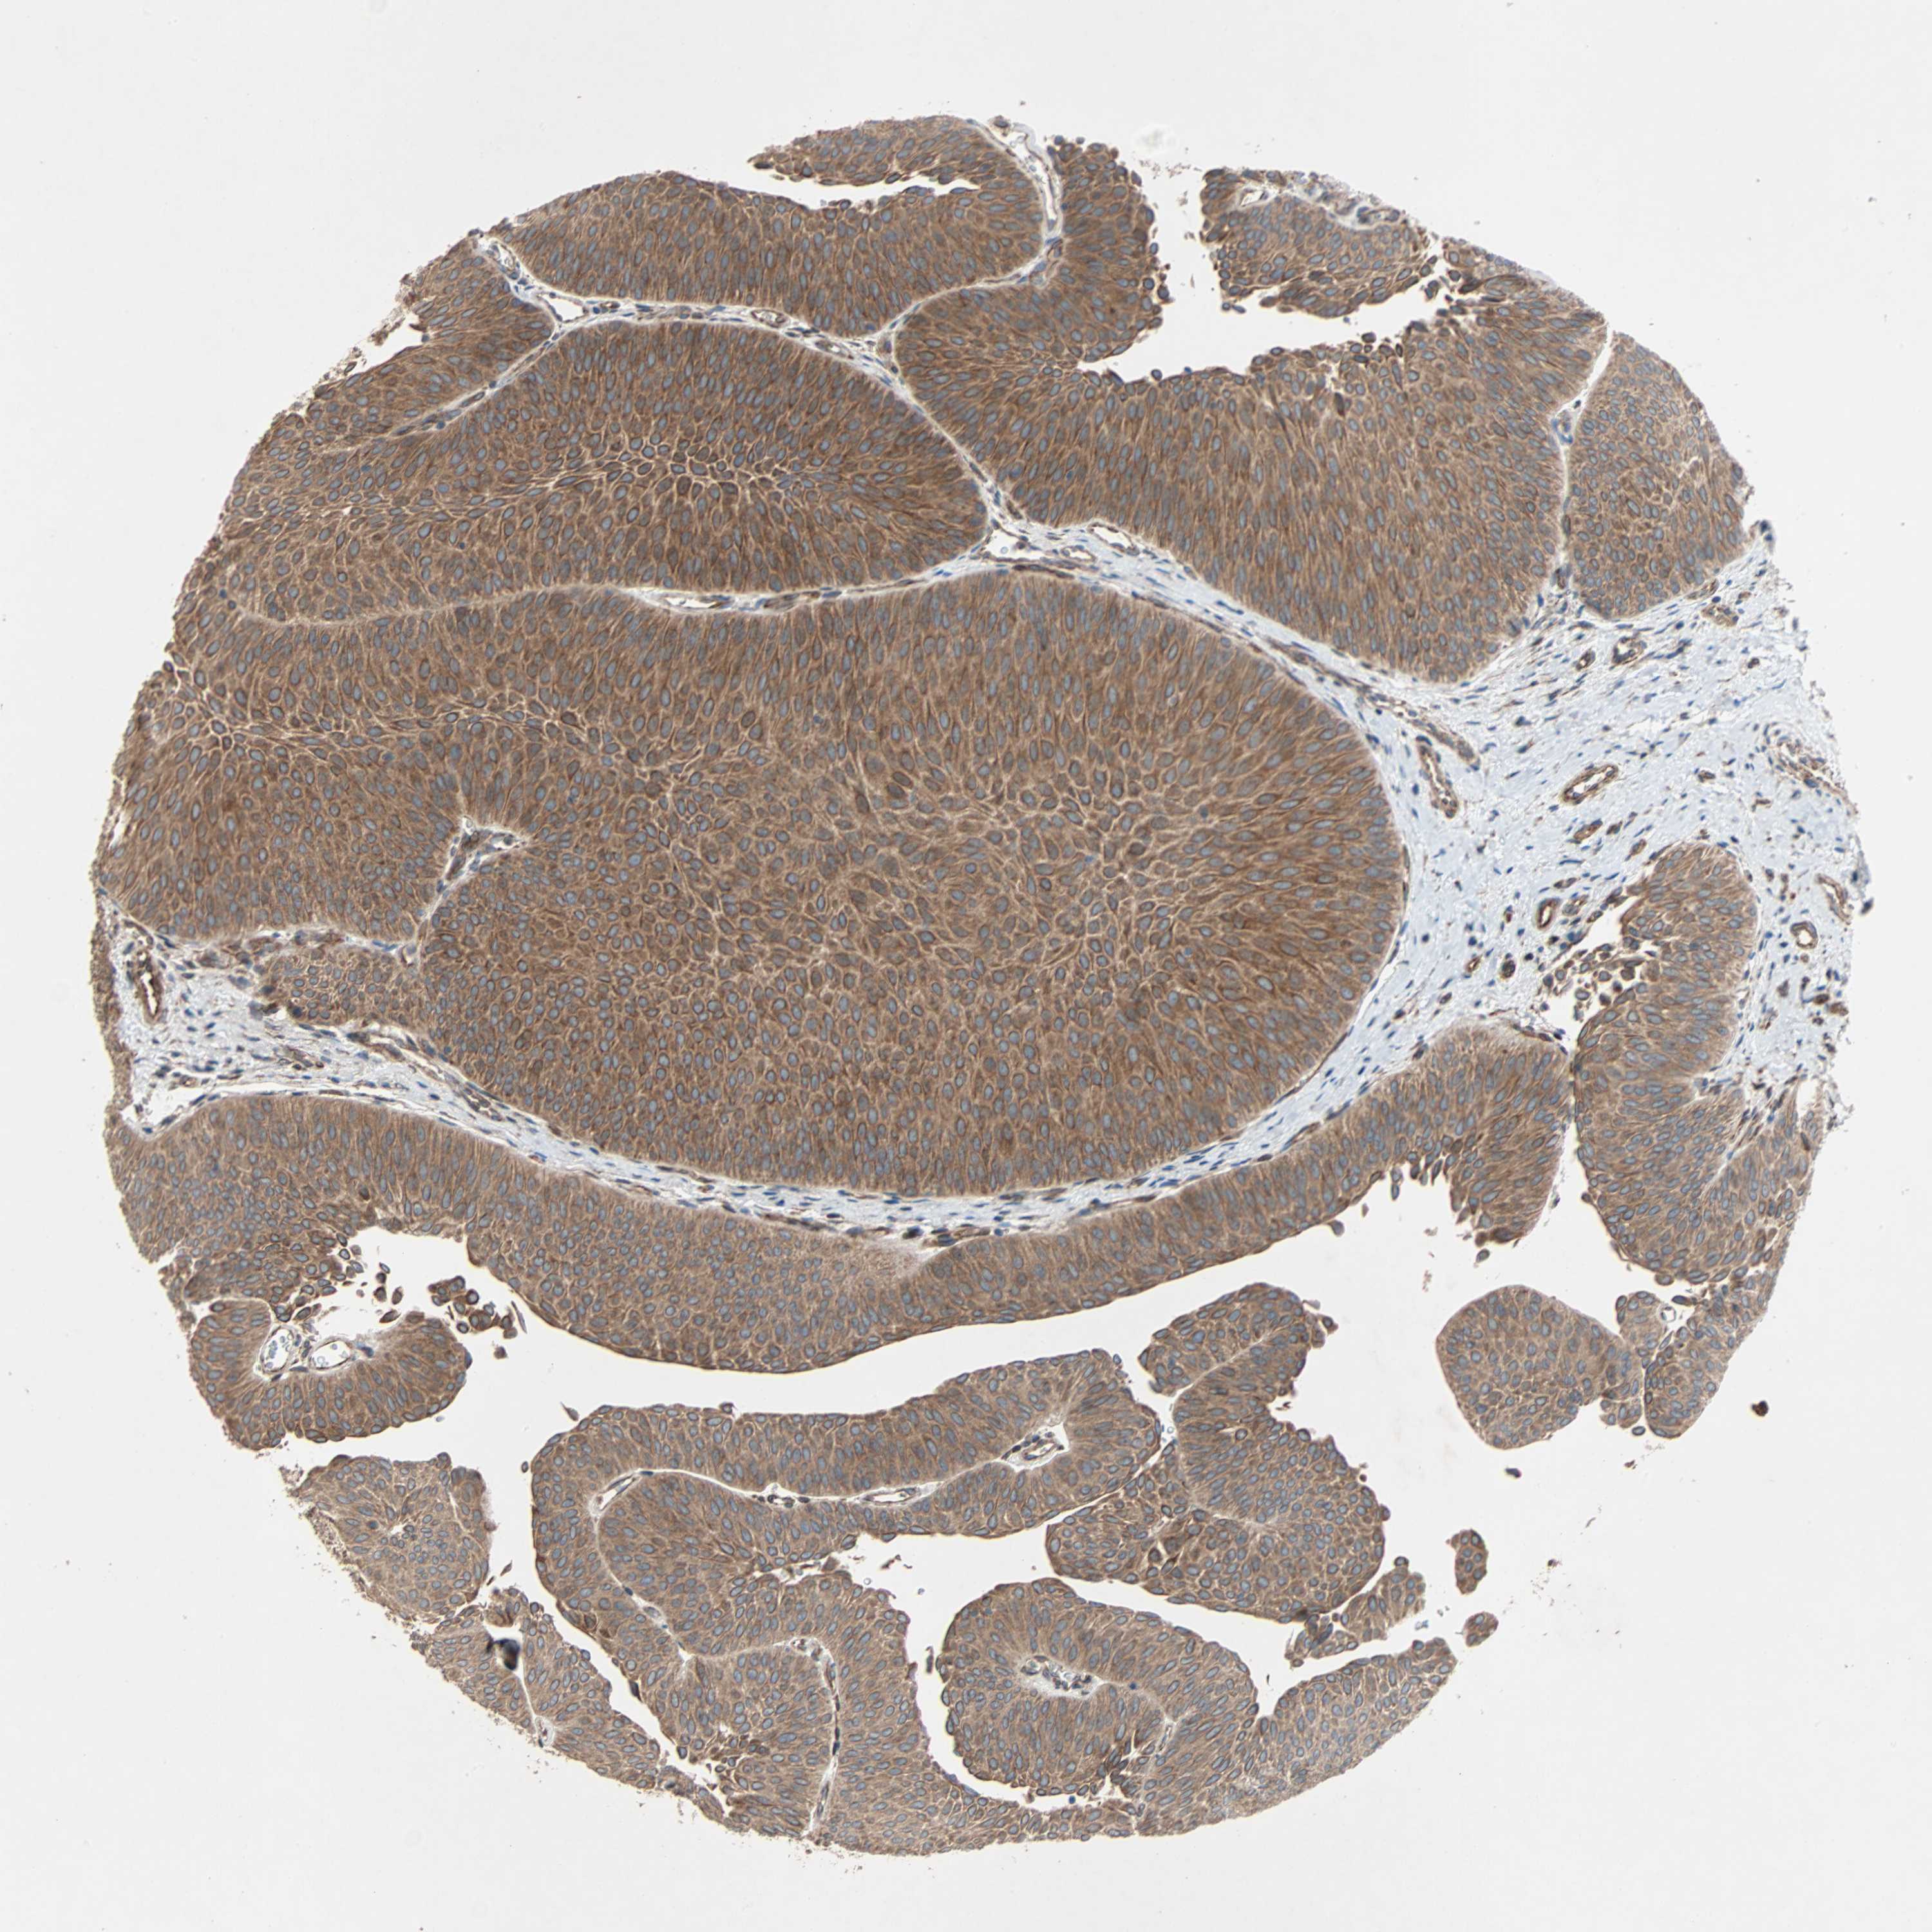

UROTHELIAL CANCER - Protein expressioni

A mouse-over function shows sample information and annotation data. Click on an image to view it in a full screen mode. Samples can be filtered based on level of antibody staining by selecting one or several of the following categories: high, medium, low and not detected. The assay and annotation is described here.

Note that samples used for immunohistochemistry by the Human Protein Atlas do not correspond to samples in the TCGA dataset.

Antibody stainingi

Antibody staining in the annotated cell types in the current human tissue is reported as not detected, low, medium, or high, based on conventional immunohistochemistry profiling in selected tissues. This score is based on the combination of the staining intensity and fraction of stained cells.

Each image is clickable and will lead to virtual microscopy that enables deeper exploration of all samples and also displays staining intensity scores, fraction scores and subcellular localization as well as patient and tissue information for each sample.

Antibody HPA007478

Antibody HPA007966

Urothelial carcinoma, Low grade

Urothelial carcinoma, High grade